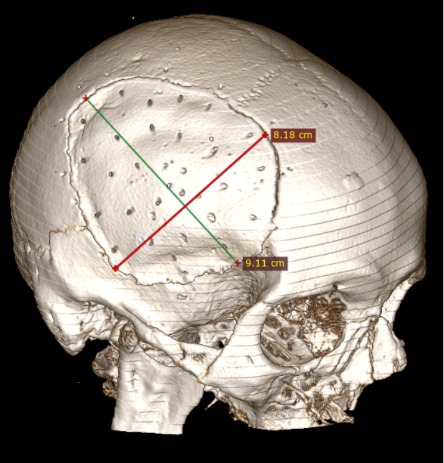

6 pav. Perforacijos KPL

Straipsnyje aptariamu atveju paciento KPL skirtinas mažiausiai (75 cm2) grupei, kuriai būdinga minimali infekcijos atsiradimo rizika (13 pav.), tačiau operacijos metu vis tiek buvo paimtas mikrobiologinis pasėlis infekcijai ekskliuduoti. Mokslinėje literatūroje taip pat pristatomas siekis tirti skirtingų pirminių galvos smegenų hematomų, po kurių reikėjo atlikti kraniektomiją, koreliaciją su EDS, tačiau reikšmingų rezultatų negauta [8].

13 pav. Kranioplastikos lopo dydis (iki 75 cm2)